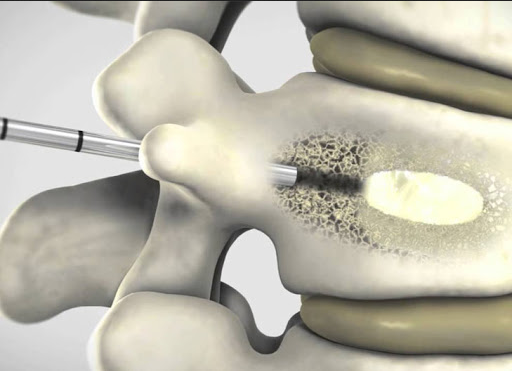

A cifoplastia percutânea é um método minimamente invasivo destinado ao tratamento de fraturas vertebrais. Este método, no entanto, não se destina ao tratamento de toda e qualquer fratura vertebral….